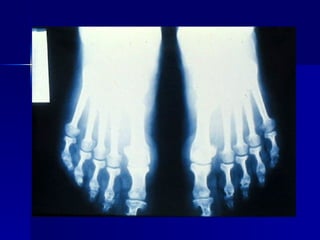

Cuadro clínico de la acromegalia 64% Hiperhidrosis 72% Oligo o amenorrea 72% Artralgias  98 % Cambios faciales, en manos y pies Mas. 48% Fem. 52% Género     8.7 años Años promedio de evolución 42 años Edad promedio al diagnóstico

Cuadro clínico dela acromegalia 64% Hiperhidrosis 72% Oligo o amenorrea 72% Artralgias 98 % Cambios faciales, en manos y pies Mas. 48% Fem. 52% Género  8.7 años Años promedio de evolución 42 años Edad promedio al diagnóstico